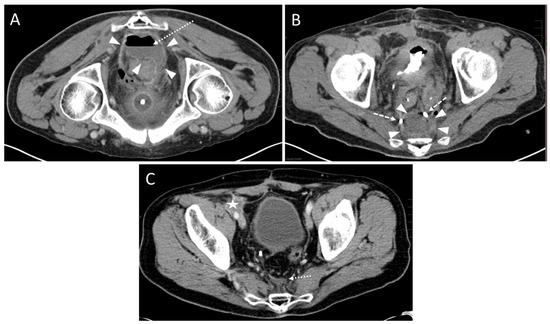

3.2. Pre- and Peri-Interventional Analysis

| Position | Count |

| Prone | 29 |

| Lateral | 11 |

| Approach | |

| parasacral | 29 (72.5%) 3 |

| paracoccygeal | 10 (25.0%) 3 |

| infracoccygeal | 1 (2.5%) 3 |